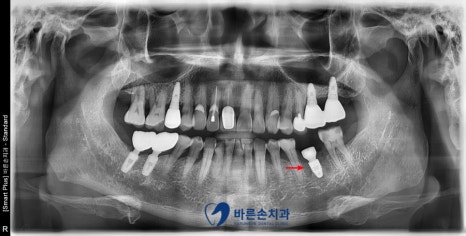

스트라우만 임플란트를 식립 후,

주변에 뼈 이식까지 잘 해줍니다.

발치부터 임플란트 수술까지

약 15분 정도 소요되었습니다.

이제 뼈랑 임플란트가 단단하게 굳을 수 있도록 2~ 3개월을 기다린 후

임플란트 보철을 만들어 드릴 계획입니다. ^^